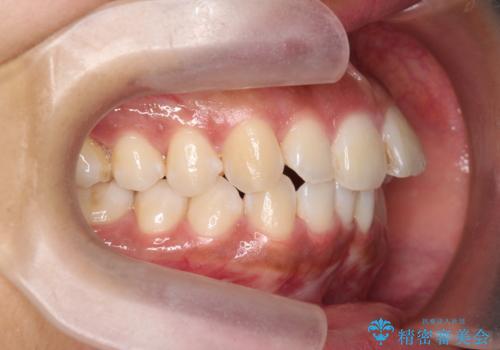

- 前歯のガタつき、突出感のある前歯の改善を求めて来院されました。

前歯の角度を改善し審美性を高めるとともに、奥歯のガタつきも並べ直すことで安定した咬合関係の確立を目指します。

歯列の側方拡大をしっかりと行ったことで歯を抜かずに前歯の角度をしっかりと改善することができました。